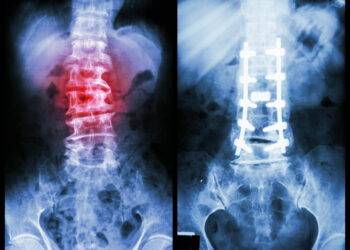

Osteoartritas – tai dažniausiai pasitaikantis sąnarių sutrikimas, kurį nulemia laipsniškas sąnarių kremzlės nusidėvėjimas. Šios ligos metu kremzlė, paprastai apsauganti sąnarinius...